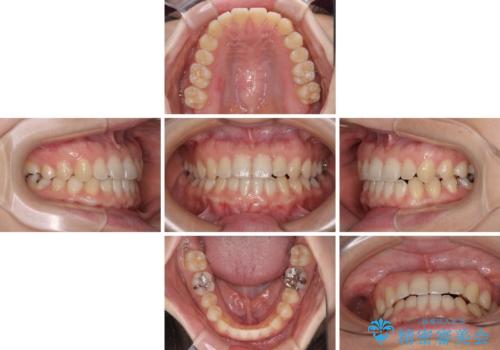

前歯のクロスバイト インビザラインによる矯正治療

インビザラインを用い、下顎歯列を後方に移動させながら全市の被蓋を改善し、歯並びを整えていくこととしました。

途中マウスピースが使用できず、来院されない期間があり、治療期間は長くかかりましたが、無事に治療を終えることができました。